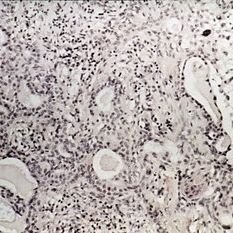

Benign lymphoepithelial lesion of Godwin. Chronic nongranulomatous inflammation of the lacrimal gland are seen, as well as epimyoepithelial islands and thickened basement membrane strands (H&E x220).

Condition/keywords: chronic nongranulomatous inflammation, epimyoepithelial islands, Godwin, lacrimal gland